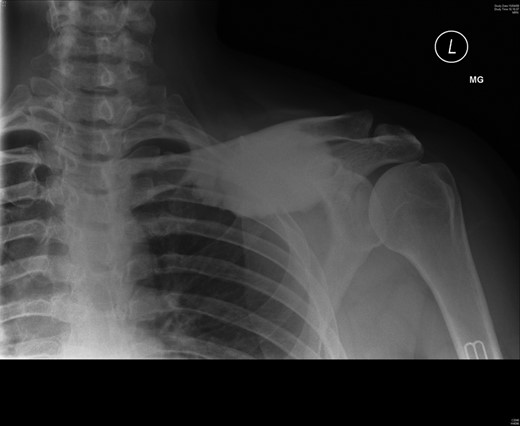

A 45-year-old woman presented with a 20-year history of a lump in the mid-third of the left clavicle, which had recently increased in size to 10 cm in diameter. Plain X-ray, computed tomography (CT) chest and clavicle, and bone scans were used to image the lesion (Figs 1–3). Radiology reported the lesion as a parosteal osteosarcoma, based on the CT appearance of tumour growing into the medulla of the mid-third of the clavicle; not usually a feature of an osteochondroma or an osteoma. Biopsies showed dense sclerotic bone, with no obvious malignant features. To confirm diagnosis complete excision of the tumour was needed, with a partial excision and scraping the lump off the surface deemed unsafe. The patient was informed that, following a total claviculectomy, a 30% functional loss (29.5% [8]) in her left shoulder power would be expected. Her active lifestyle meant this result was unacceptable, so she opted instead for excision of the tumour plus the adjacent clavicle, irradiation and reimplantation of the bone with internal fixation, despite this being relatively experimental. If successful, she would have virtually normal function. Although possible risks included infection or development of non-union, which would require further surgery or possible complete claviculectomy, it was deemed oncologically safe with a low risk of complications.